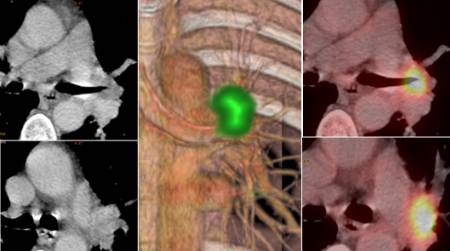

Sin embargo, el campo en el que menos se ha avanzado en estos años ha sido en el uso integral y completo de las dos técnicas que conforman esta exploración diagnóstica: el PET y el CT.

Según el responsable de Medicina Nuclear e Imagen Molecular de ambos centros de Quirónsalud, la inmensa mayoría de los Servicios focalizan los estudios únicamente en la vertiente PET, sin considerar la valiosa información que puede proporcionar la imagen morfológica CT. "El radiólogo apenas participa en la interpretación de estos estudios, sacando conclusiones básicamente de la información metabólica y de forma escasa de la morfológica del CT. Pocos son los radiólogos que colaboran estrechamente con los médicos nucleares en la confección de los informes de los estudios PET-CT, con la consiguiente y lógica perdida de información que el CT puede proporcionar", afirma Antonio Maldonado.

Imagen en alta resolución. Este enlace se abrirá mediante lightbox, puede haber un cambio de contextoPor ello, el Departamento de Medicina Nuclear e Imagen Molecular del Hospital Universitario La Luz y del Hospital Universitario Quirónsalud Madrid, lidera el uso al 100% de la tecnología PET-CT entre los médicos nucleares y radiólogos.

El experto explica que desde 2003 (fecha de la introducción de la PET-CT en España) ha liderado proyectos PET-CT donde han colaborado los especialistas de Medicina Nuclear y Radiodiagnóstico en la realización de estas pruebas de imagen médica. "Aspectos tan importantes como el uso de protocolos CT diagnósticos, la realización de un único informe mixto metabólico/morfológico y conclusiones prácticas e integradas que solucionen las preguntas de los oncólogos son las piezas claves de nuestra forma de actuar. Evitamos pruebas radiológicas innecesarias, hacemos de cada estudio una pequeña sesión clínica médico nuclear/radiólogo, intentando dar la mejor respuesta clínica a los médicos que nos piden las pruebas", matiza el doctor Maldonado. Como afirma el especialista en Medicina Nuclear, las conclusiones de nuestros informes poseen una gran orientación clínica e intentan servir de ayuda en la toma de decisiones en el manejo del paciente oncológico.

"Para nosotros, interpretar un PET-CT es un arte y cada día que pasa intentamos mejorarlo", subraya el doctor. Esta sistemática de trabajo es la que se aplica en los equipos PET-CT que dispone el Departamento tanto en el Hospital Universitario La Luz como en el Hospital Universitario Quironsalud Madrid. "La colaboración médico nuclear-radiólogo es la pieza angular de nuestra actividad diaria", concluye el doctor Antonio Maldonado.